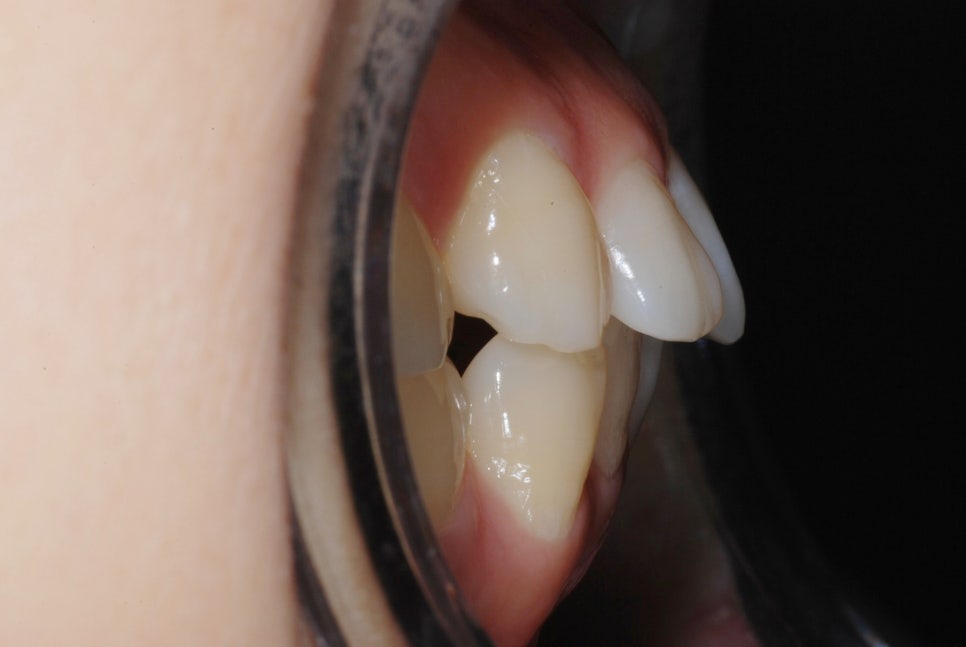

In this patient’s case, the biggest concern was an underbite with the lower jaw developed forward.

As a result of the diagnosis, the teeth were unevenly positioned due to insufficient space,

and because of mandibular overgrowth, the lower front teeth protruded beyond the upper front teeth.

Around 12 months later, the extraction spaces had closed, and you can see that the teeth were moving inward well.

The treatment period was about 1 year and 6 months,

and before treatment, the lower jaw looked more prominent when speaking or smiling,

after treatment, it changed to a much softer and more natural appearance.